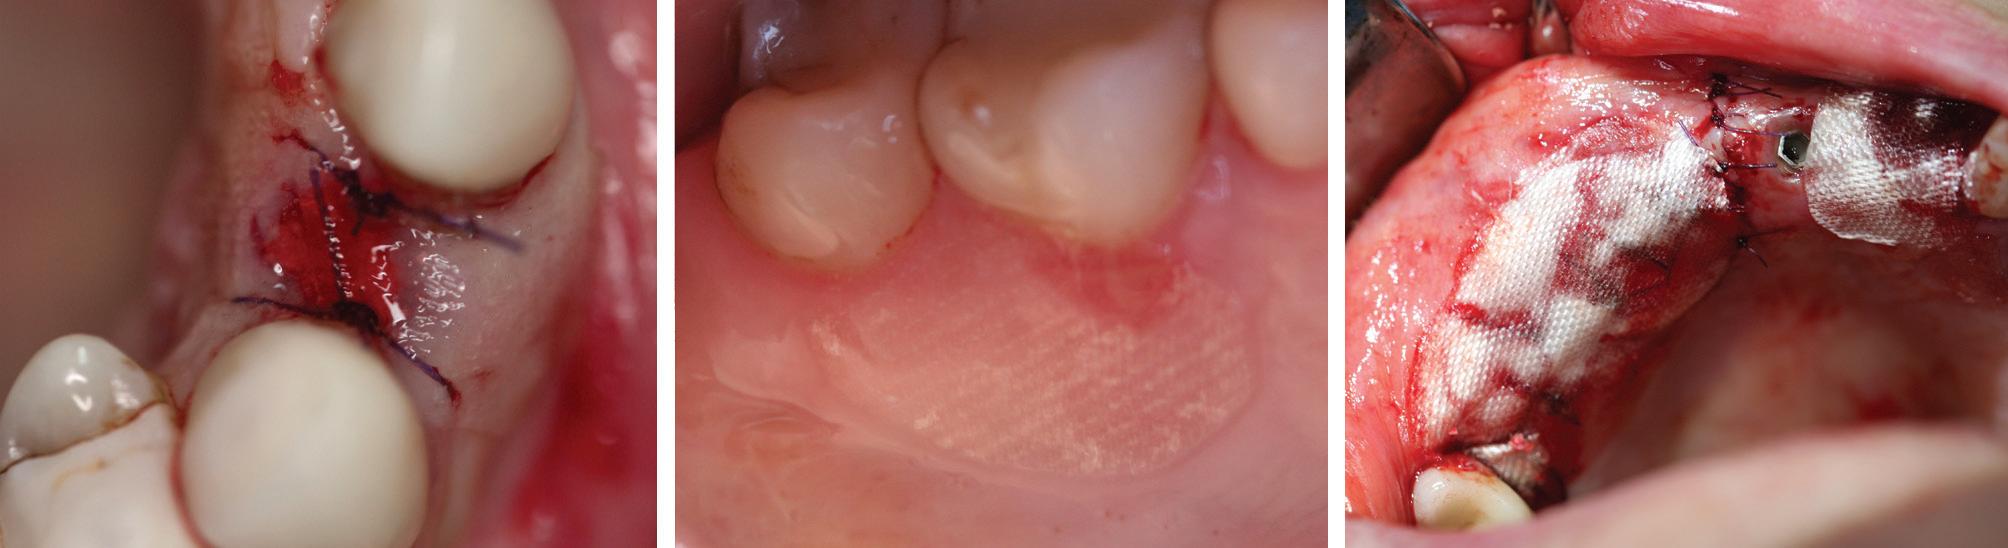

R.T.R.+ in practice: Managing the extraction socket

130 Case report: Managing the extraction socket with R.T.R.+ and a connective tissue graft